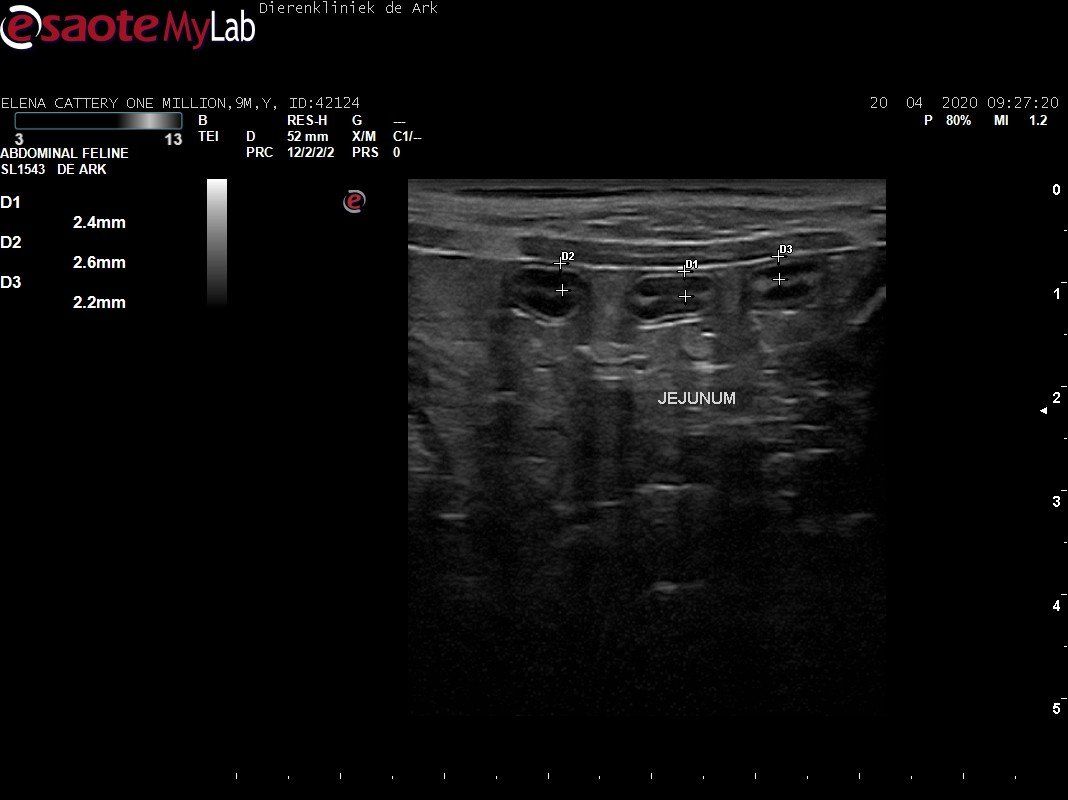

3,200 kg , echo en nieuw bloedonderzoek gedaan wat perfect ging door middel van gapabetine

Voor de garanties en om recht te hebben op medicatie bij herval eist Mutian diverse onderzoeken en controle momenten. Dit zijn bloedonderzoeken maar ook zoals hieronder te zien is echo's. Elana is volledig gecontroleerd op afwijkingen, gelukkig waren de echo's goed.